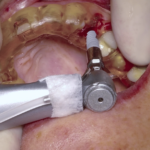

Rehabilitación completa maxilar (Full Arch)

Paciente: mujer, 59 años, edentulismo parcial.

Tratamiento: colocación de 6 implantes inmediatos con férulas apilables y prótesis provisional instantánea parcial.

Tiempo de intervención: 2 horas y 30 minutos.

Beneficios: intervención rápida y precisa, manejo conservador del tejido blando, estética y funcionalidad instantánea, alta satisfacción del paciente.

Estos casos ilustran cómo nuestro flujo BRDP y la cocreación clínica permiten resultados predecibles y eficientes, optimizando tanto el tiempo de sillón como la experiencia de paciente y clínica.